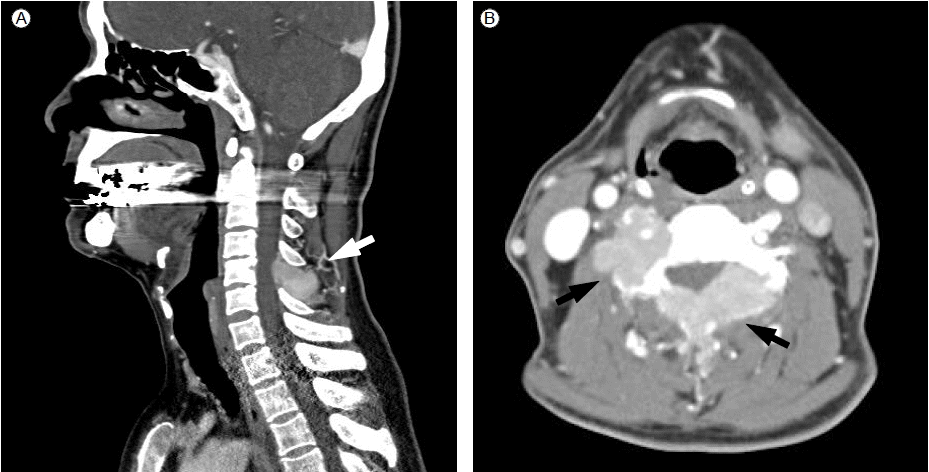

Figure 1.

(A) Computed tomography shows a 4.3 × 2.6 cm soft-tissue mass with destruction of the posterolateral arc of the right 6th rib (arrow). (B) Magnetic resonance imaging shows an enhancing 6.8 × 4.5 × 7.8 cm soft tissue mass in the right iliac bone adjacent to the sacroiliac junction (arrow). A biopsy of the mass in the right 6th rib revealed diffuse infiltration of plasma cells that are positive for CD 138 (C) and lambda light chain (D) on immunohistochemical staining (×400).